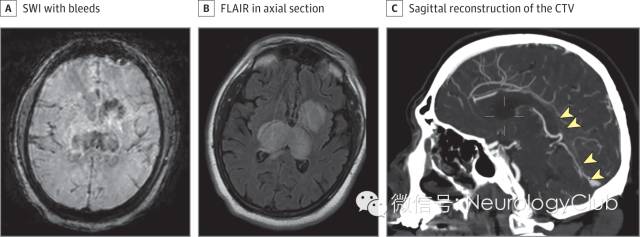

60余岁男性,既往有房颤病史,服用华法林治疗,表现为意识模糊和嗜睡3天。国际标准化比值(INR)为2.07。无感染或代谢异常的证据。脑脊液压力260mmH2O,常规及生化均正常。患者意识模糊加重,头颅MRI和CT静脉造影提示丘脑和基底节区巨大梗死伴出血,直窦充盈缺损(图)。启动抗凝治疗,但患者在住院3天后去世。

(图:硬脑膜的直窦血栓形成和双侧大脑半球深部梗死。A:磁敏感加权成像[SWI]提示双侧丘脑及左侧基底节区出血;B:FLAIR双侧丘脑,基底节区和内囊,以及胼胝体压部高信号,水肿明显;C:CT静脉造影重建可见直窦,Galen静脉和下矢状窦远端充盈缺损[箭头])

大脑直窦血栓形成